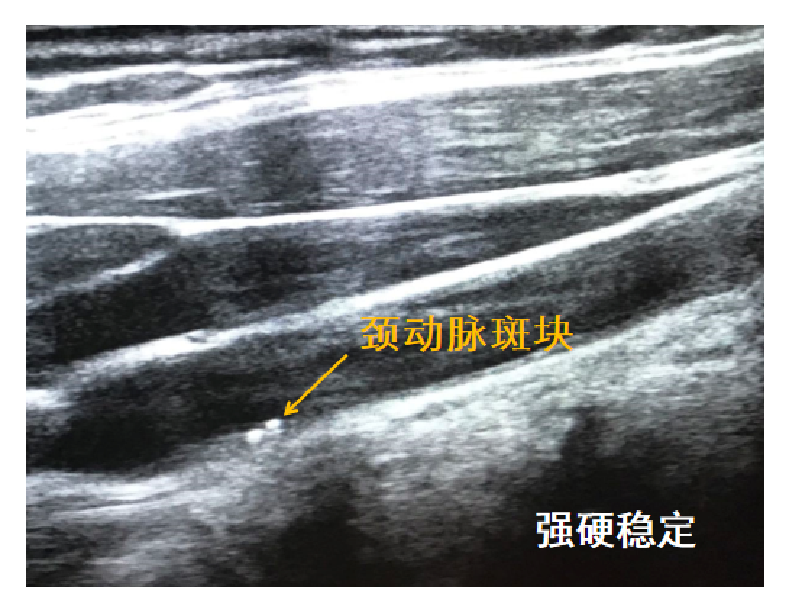

怎么知道身体里的血管有没有动脉粥样硬化呢?通常最简单而又无创的方法是做颈部动脉的超声检查,因为颈动脉就在颈部的体表,超声可以很清楚地看到颈动脉及其分支处。如果颈动脉见到斑块,提示全身大大小小的动脉血管均有斑块形成。

颈动脉的硬斑块